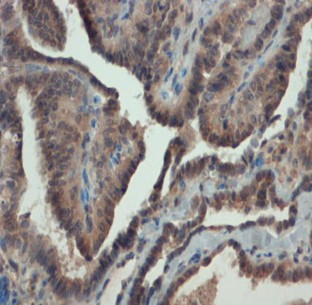

The objective of this study is to examine the expression of matrix metalloproteinase 1 (MMP-1) in invasive well-differentiated thyroid carcinoma (WDTC) and its relation to clinicopathological features. This retrospective case study group included 26 patients with invasive WDTC who were treated at our center between January 1985 and May 2007. Clinical data were collected from the medical files. MMP-1 expression was tested in samples from paraffin-embedded tumor by immunohistochemical staining. MMP-1 expression correlated with laryngotracheal invasion (p = 0.032), multifocality of the tumor (p = 0.044), and presence of regional (p = 0.034) and distant metastases (p = 0.048). In conclusion, the expression of MMP-1 in invasive WDTC is consistent with tumor aggressiveness, manifested by laryngotracheal invasion, multifocality, and regional and distant metastases. MMP-1 expression may serve as a prognostic marker and an indicator for the need for more aggressive surgical treatment.